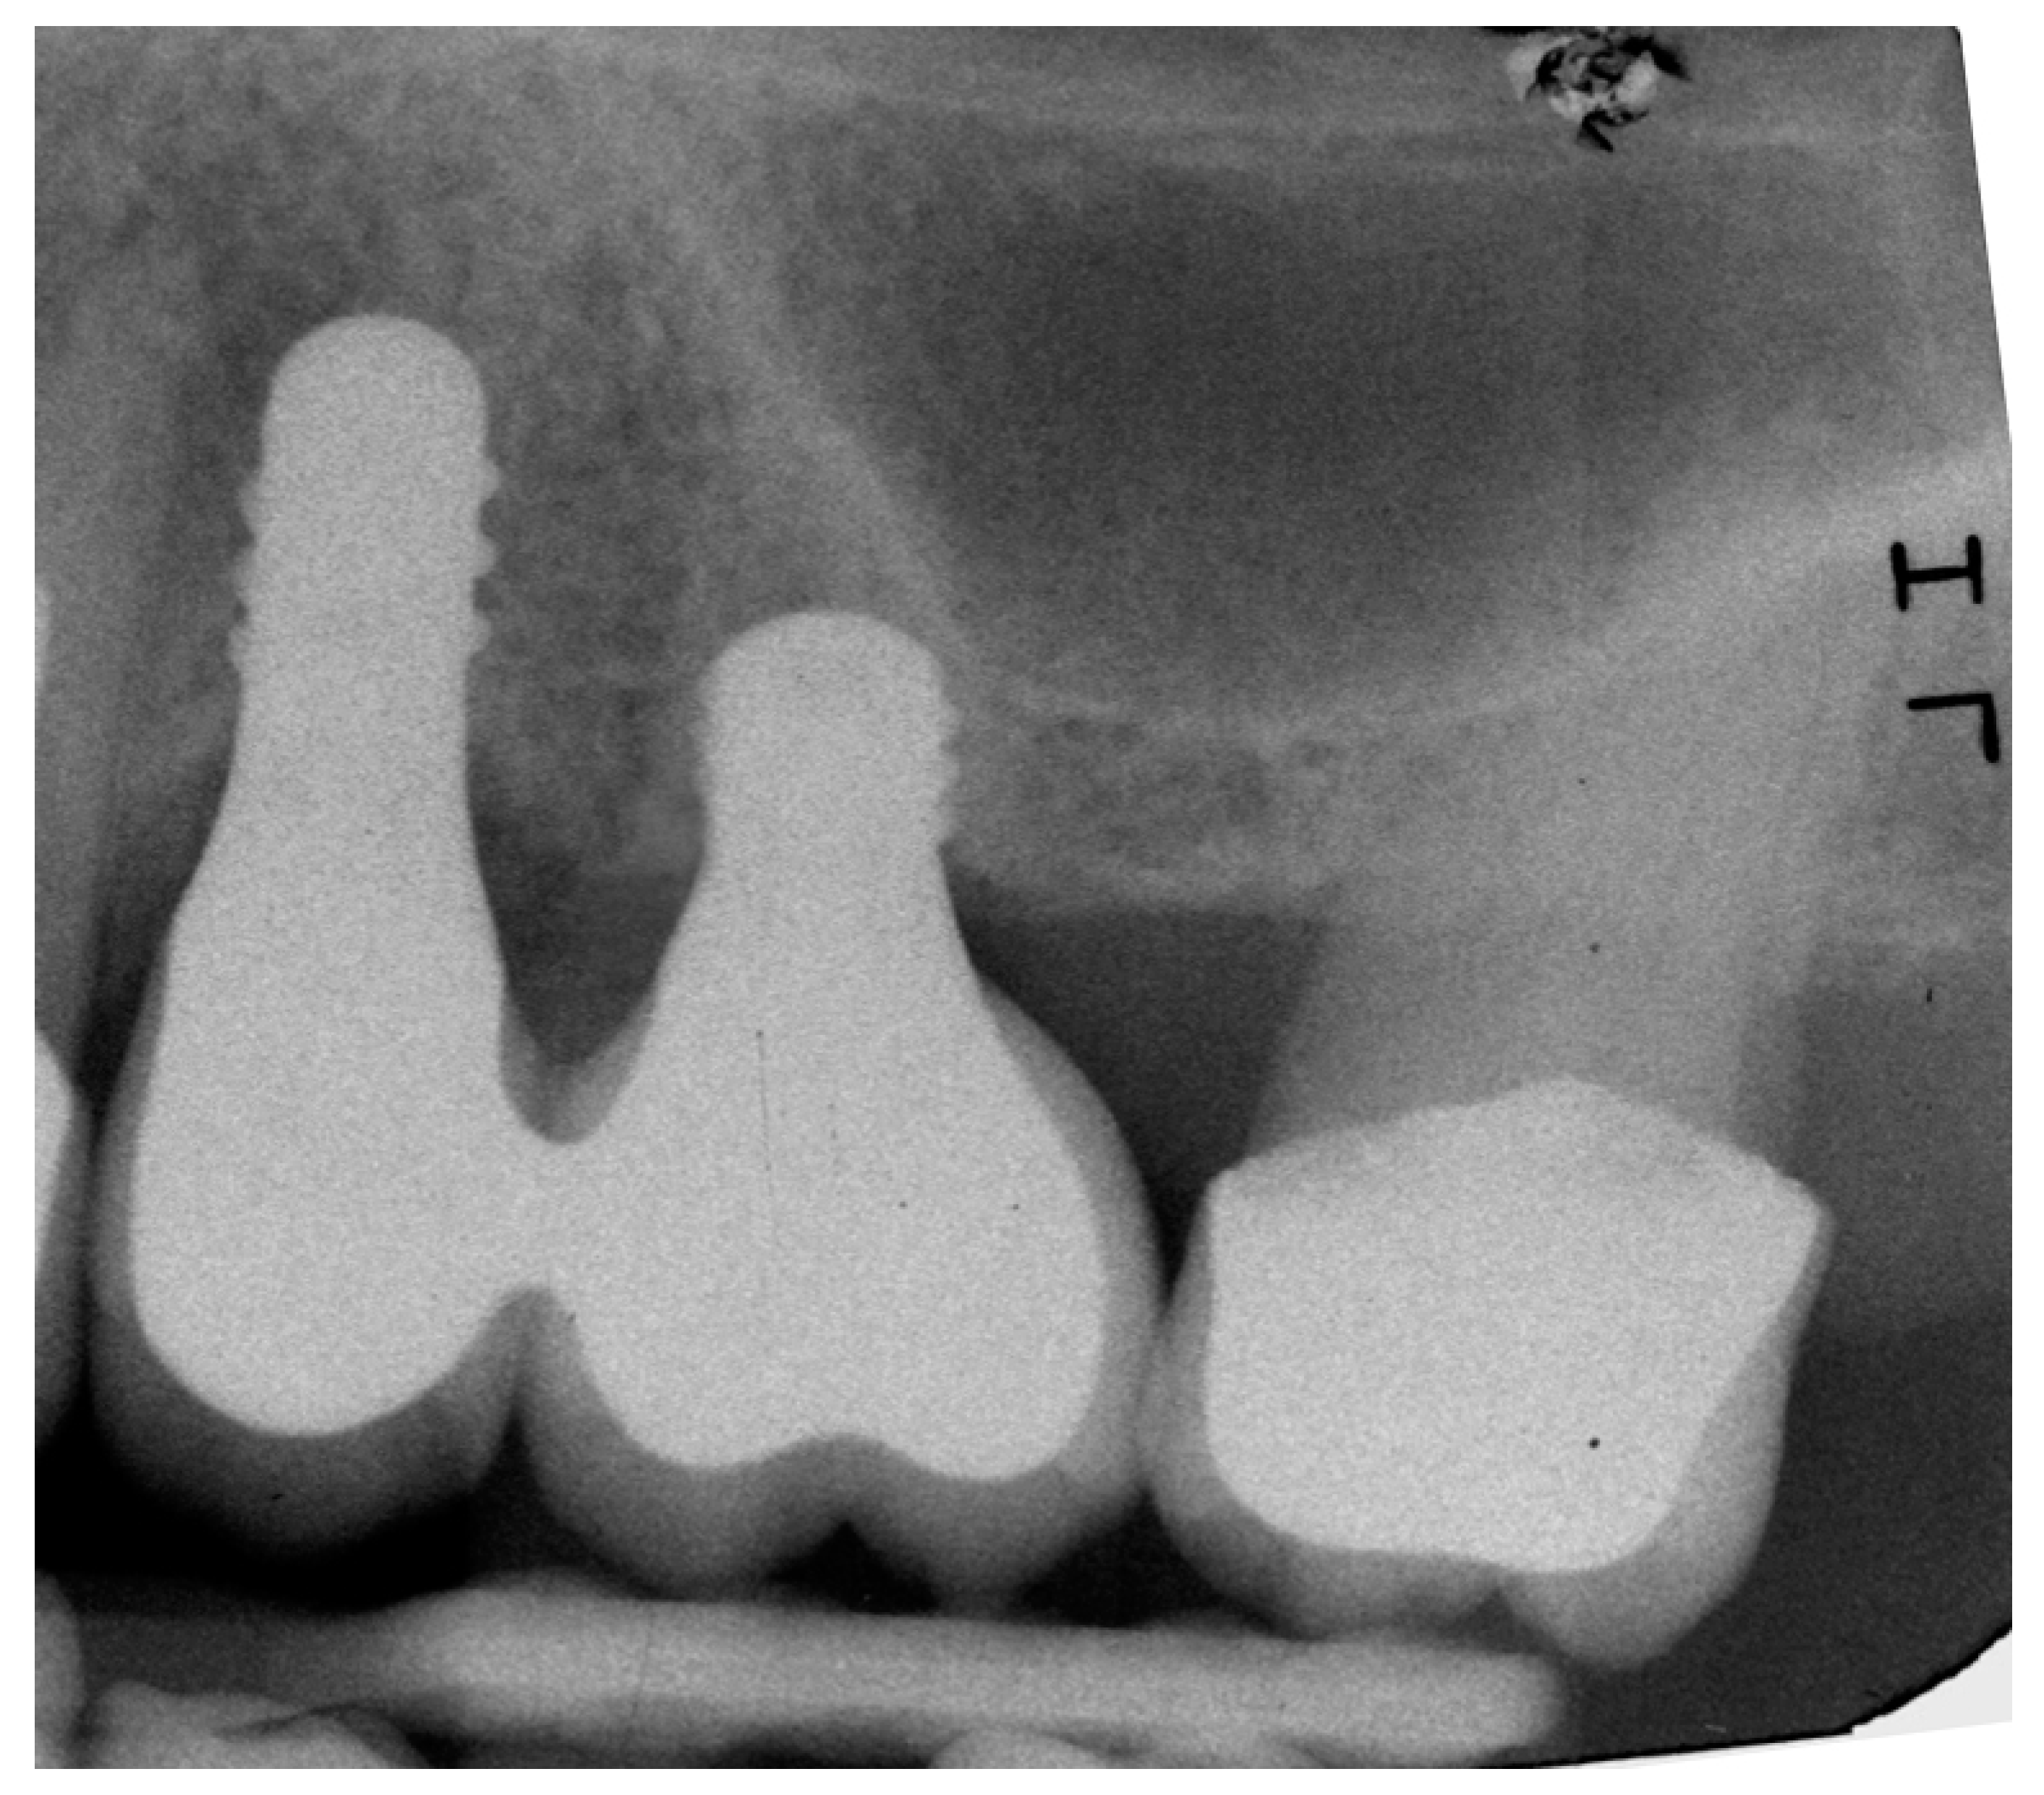

4.1. Marginal Bone Level (MBL)

4.2. Bone tissue remodeling (MBL change)